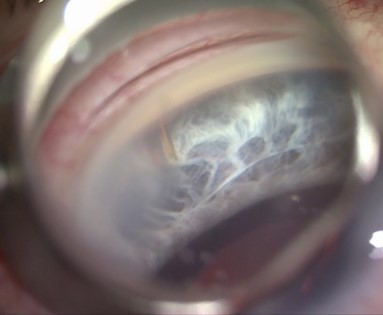

Es handelt sich hierbei um ein sechs Millimeter langes kleines Gelatineröhrchen mit einem Innendruckmesser von 45 Mikrometer oder 63 µm, das die überschüssige Flüssigkeit aus dem Auge unter die Bindehaut ableitet und damit den Augendruck senkt. Das Wirkprinzip ist vergleichbar mit der einer Filterkissenoperation. Im Gegensatz zu anderen aufwändigeren operativen Verfahren wird das Auge dabei nur minimal verletzt und die Bindehaut nicht aufgeschnitten. Zudem ist der Eingriff von kurzer Dauer und kann auch in lokaler Betäubung vorgenommen werden. Da der drucksenkende Effekt nicht ganz so hoch wie bei der Trabekekulektomie oder Drainageimplantaten ist, ist dieser Eingriff nicht für alle Glaukomformen geeignet. Erfahrungen mit diesem sehr häufig eingesetzten Stent haben wir seit über 8 Jahren. Die größte Komplikationsgefahr besteht in einer Vernarbung der Abflußzone unter der Bindehaut, die zu einer Revisionsoperation in 20% der Fälle führen kann. Die Vernarbung kann man nur mit Hilfe von antientzündlichen Augentropfen und Spritzen unter die Bindehaut im Verlauf nach der Operation beeinflussen aber leider nicht immer verhindern.